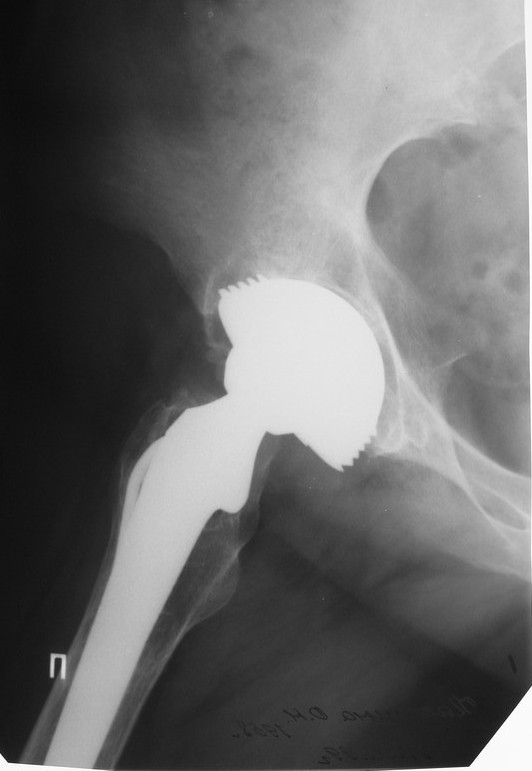

Уважаемые коллеги,в клинику поступила пациентка 51год с нестабильным антипротрузионным кольцом и вывихом эндопротеза. В течени длительного времени у пациентки ревматойдный полиартрит с приемом преднизолона. В 1994 году произведено эндопротезирование правого тазобедренного сустава бесцементным эндопротезом Biotronic. В 2000году по поводу нестабильности эндопротеза проведено ревизионное вмешательство-удаление чашки и ножки, некрэктомия. Установка антипротрузионного кольца, цементной чашки и ревизионной цементной ножки Beznoska. В 2007году выявлена клиникорентгенологическая картина нестабильности кольца. В 2008году пациентка упала, произошел вывих эндопротеза и дислокация кольца с переломом винтов. Планируем ревизионное вмешательство-удаление кольца, чашки, винтов, пластика верхнего края вертлужной впадины массивным аллотрансплантатом с последующей установкой антипротрузионного кольца типа Burch-Shneider. Прошу коллег занимающихся ревизионным эндопротезированием высказать свое мнение.PS:у больной в 1998 году установлен цементный эндопротез Beznoska левого тазобедренного сустава и в 2003 году установлен цементный эндопротез De Puy LCS правого коленного сустава.

Ситуация непростая, во время операции может оказаться дефект не только передне-верхнего отдела ВВ, но и слабость задней стенки. В этом случае результаты установки кольца Б-Ш могут быть не столь оптимистичны. Использование массивного аллографта опасно развитием позднего остеолиза и как следствие - нестабильности конструкции, плюс к этому-реальная опасность инфекционного осложнения. В последнее время (и мы будем говорить об этом на Вреденовских чтениях - маленькая рекламка:)) мне все больше импонирует ТМТ, это трабекулярный металл с очень высокой пористостью. Если рим ВВ позволяет хоть немного зацепиться полусферической чашкой, то успех гарантирован. При наличии сегментарного дефекта лучше в этой ситуации использовать трабекулярные аугменты и женить с ТМТ ревизионной чашкой при помощи цемента. Все небольшие дефекты мы заполяем костной стружкой (алло) в последнее время стали применять остеосет Т (с тобромицином). Если же совсем все плохо, то тогда палочкой-выручалочкой является кольцо Б-Ш., которое можно установить по ситуации, а анатомические углы выставить ПЭ вкладышем.